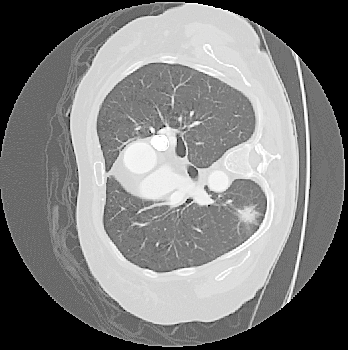

Top row: An image slice demonstrating the lung Isolation process, enacted on a low dose spiral CT scan taken from the LIDC-IDRI database.

- Method Overview: In each CT scan, the internal 3D lung volume was isolated using standard thresholding of pressurevalues ranges associated with lung parenchyma. The remaining voxels were conjoined using a connected components method, implemented through a union-find method, with small and isolated components removed. The remaining gaps were filled in using a standard 3D image closure method. First and second order partial derivatives were computed using Deriche filters, chosen for their stability and suitability in medical image scans. Then, for each of the voxels in the internal volume of the lung the local second order Image Hessian was generated and analyzed for preferred directions using eigenanalysis. This information was then used to weight the contribution of each voxel to standard lung nodule detection methods, to determine if giving stronger weight to voxels with local blob-like shape improved detections results.